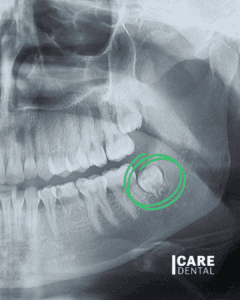

Wisdom teeth coming in? We can help with that! 🦷 We perform tooth extractions with precision at Care Dental. 🔎✅

- Impaction: Wisdom teeth often don’t have enough space to emerge properly. This can lead to impaction, where the teeth are unable to grow in fully or in the right position. Impacted wisdom teeth can cause pain, infection, and damage to neighboring teeth.